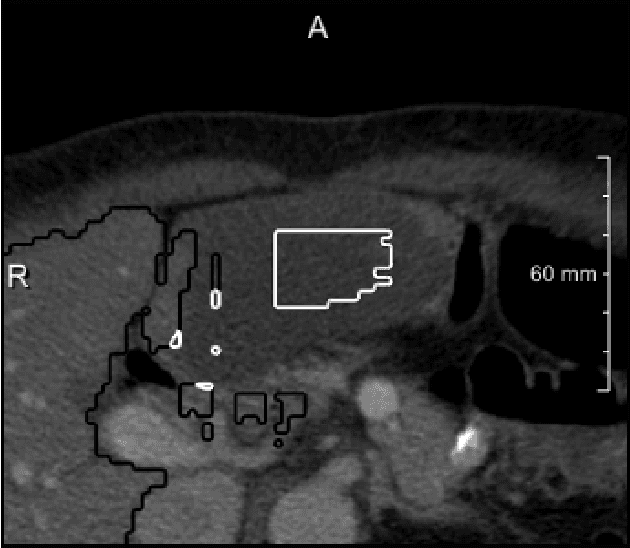

Abstract:Semantic segmentation neural networks require pixel-level annotations in large quantities to achieve a good performance. In the medical domain, such annotations are expensive, because they are time-consuming and require expert knowledge. Active learning optimizes the annotation effort by devising strategies to select cases for labeling that are most informative to the model. In this work, we propose an uncertainty slice sampling (USS) strategy for semantic segmentation of 3D medical volumes that selects 2D image slices for annotation and compare it with various other strategies. We demonstrate the efficiency of USS on a CT liver segmentation task using multi-site data. After five iterations, the training data resulting from USS consisted of 2410 slices (4% of all slices in the data pool) compared to 8121 (13%), 8641 (14%), and 3730 (6%) for uncertainty volume (UVS), random volume (RVS), and random slice (RSS) sampling, respectively. Despite being trained on the smallest amount of data, the model based on the USS strategy evaluated on 234 test volumes significantly outperformed models trained according to other strategies and achieved a mean Dice index of 0.964, a relative volume error of 4.2%, a mean surface distance of 1.35 mm, and a Hausdorff distance of 23.4 mm. This was only slightly inferior to 0.967, 3.8%, 1.18 mm, and 22.9 mm achieved by a model trained on all available data, but the robustness analysis using the 5th percentile of Dice and the 95th percentile of the remaining metrics demonstrated that USS resulted not only in the most robust model compared to other sampling schemes, but also outperformed the model trained on all data according to Dice (0.946 vs. 0.945) and mean surface distance (1.92 mm vs. 2.03 mm).